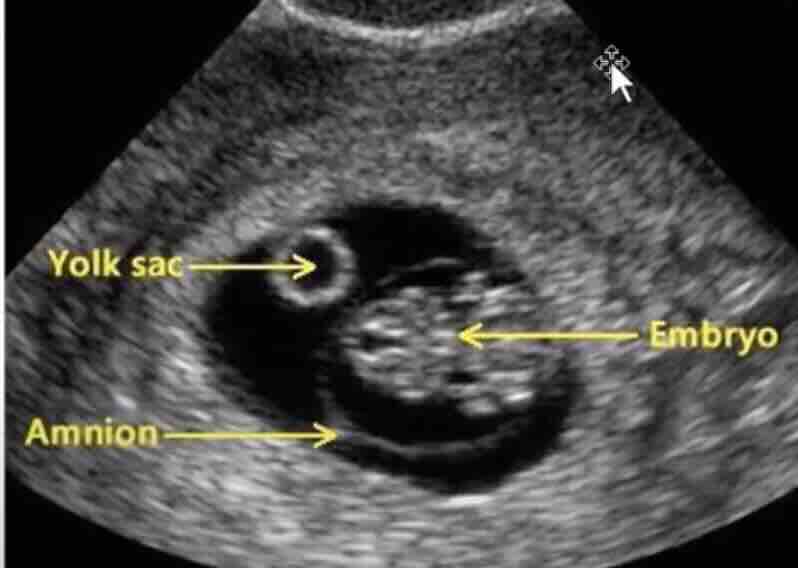

Vajinal ultrasonda gebelik kesesi görülmeye başlar (ortalama 5-6 mm).

Yolk kesesi henüz görülmeyebilir.

6. Hafta

Yolk kesesi net görülür (5.5-6. hafta).

Embriyo görülmeye başlayabilir.

Kalp atışı bazen bu haftada, bazen 7. haftada başlar.

Düşük belirtisi: Embriyo veya kalp atışının olmaması, düzensiz kese.

6. Ultrason Kriterleri: Kesin Düşük Nasıl Anlaşılır?

Erken gebelik kaybında en kesin bilgi ultrason ile elde edilir. Aşağıdaki bulgular kesin düşük tanısı koydurur:

Kesin Düşük Bulguları:

CRL (baş-popo mesafesi) ≥7 mm olduğu halde kalp atışı yok

Gebelik kesesi ≥25 mm olduğu halde embriyo yok (boş gebelik)

Embriyo varken kalp atışı daha önce varken sonra durmuşsa

İki ultrason kontrolü arasında embriyo hiç büyümemişse